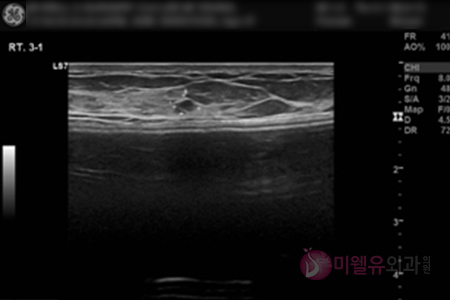

유방초음파 오른쪽 정상소견